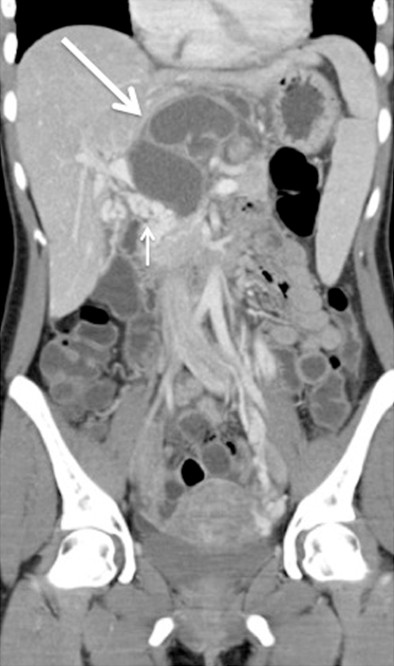

Patient #2

A 27-year-old Maroccan born female, living in Belgium, was admitted for fever of unknown origin. Other symptoms included weight loss, continuous epigastric and right upper quadrant pain for three months. Upon admission, abdominal ultrasound showed a large cystic lesion around the liver hilum associated with a portal cavernoma. Abdominal CT scan followed by abdominal MRI confirmed the presence of a heterogeneous polycystic mass adjacent to the pancreas within the lesser sac without dilatation of the main pancreatic duct (Figure 2). The patient underwent EUS-FNA, which allowed the aspiration of a yellowish purulent liquid, a sterile exudates rich in neutrophils upon analysis. Surgical resection of the cyst was scheduled based on the suspected diagnosis of an infected mucinous cystadenoma; the day before the surgery a positive result for M. Tuberculosis culture from the cyst fluid was received. Chest CT scan was normal. The patient was put on anti-tuberculin therapy, her symptoms resolved quickly. Control CT showed a significant decrease of para-pancreatic lesion.

|

Figure 2. Contrast enhanced MDCT coronal reformat shows a large multicystic, septated lesion located in the lesser sac (long arrow). Associated cavernous transformation of the portal vein is seen (short arrow) (Patient #2). |